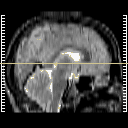

[Home][Help][Clinical] Slice 14

Click on sagittal image to select slice. Click on thin tickmark to change timepoint, or thick tickmark for overlay.